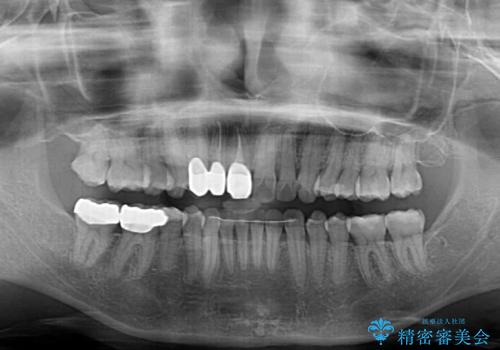

- 前歯の歯並びやむし歯治療の跡、奥歯の銀歯を気にして来院された患者様です。

インビザラインによる矯正治療の後に虫歯や銀歯をセラミックにて補綴することとしました。

前歯のむし歯治療の跡や奥歯の目立つ銀歯がなくなり、明るい口元になりました。